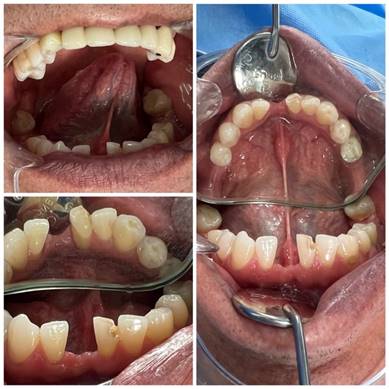

Se presenta el caso de un paciente masculino de 58 años que se presentaba sensibilidad en los órganos dentarios anteriores en lingual y molestias al momento del habla. El paciente no reportó antecedentes patológicos de relevancia. Al practicar el examen estomatológico se observó que el paciente presentaba recesión lingual en los dientes anteriores, determinando que la causa del mismo era debido al frenillo lingual, en donde la primera manifestación clara fue que el paciente no podía colocar su lengua en el paladar, y que al momento de hacerlo, la inserción del frenillo lingual causaba tensión y generaba recesión, por lo que se indicó una frenectomía lingual para evitar mayor recesión, mejorar la movilidad lingual y brindar beneficios del habla.

Se remitió al paciente a las clínicas odontológicas de UNIANDES, sede Ambato, edificio Dra. Corona Gómez PhD para realizar el tratamiento de frenectomía lingual. Una vez explicado el procedimiento al paciente de manera verbal y escrita a través del consentimiento informado, se programó la fecha quirúrgica (Figura 1).

Figura 1. Fotografías Intraorales del Paciente.

Elaboración: Los autores.